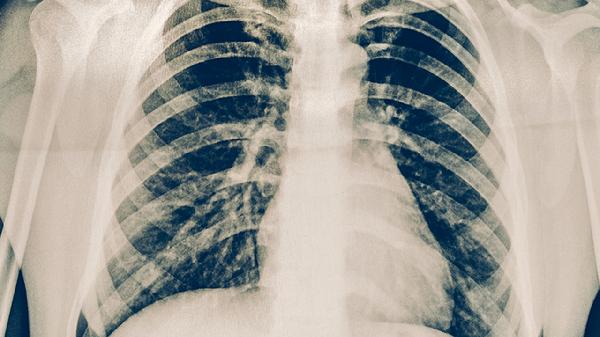

肺癌淋巴转移属于疾病进展期,生存时间受多因素影响。局限在肺门淋巴结转移且对治疗敏感的患者,通过手术联合放化疗可能获得较长时间生存。若转移至纵隔或锁骨上淋巴结,生存期往往缩短。小细胞肺癌淋巴转移进展较快,非小细胞肺癌中腺癌对靶向治疗反应较好者生存期相对延长。年龄较轻、体能状态评分高、无其他器官转移的患者预后更优。规范化疗方案如培美曲塞联合顺铂可控制病情,免疫治疗药物如帕博利珠单抗能改善部分患者生存质量。定期复查胸部CT和肿瘤标志物监测有助于评估治疗效果。